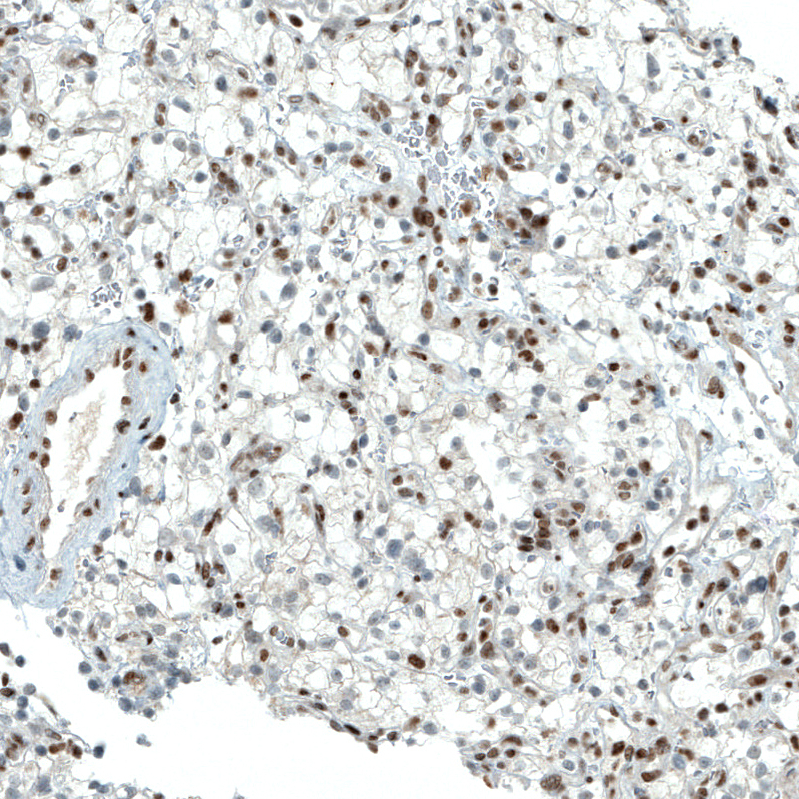

Immunohistochemistry analysis in human endometrium and skeletal muscle tissues using AMAb90690 antibody. Corresponding PBRM1 RNA-seq data are presented for the same tissues.